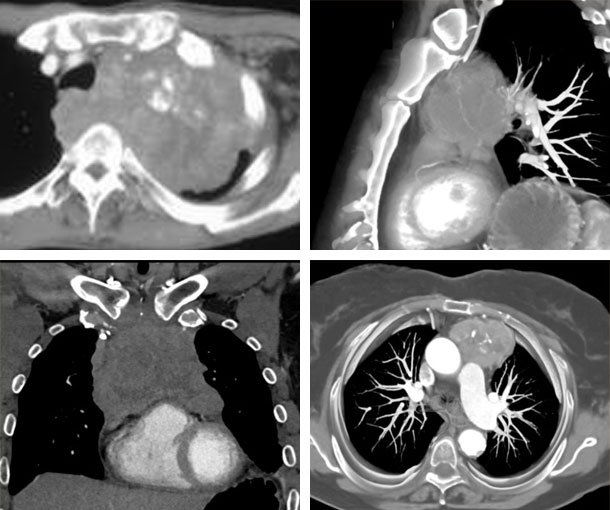

Chest CT Appearances

Thymic Carcinoma CT Findings

- Large prevascular mass

- Irregular shape

- Poorly marginated borders

- Areas of cystic change

- May have necrosis and/or hemorrhage

- “Drop metastases” indicate thymic carcinoma over lung cancer